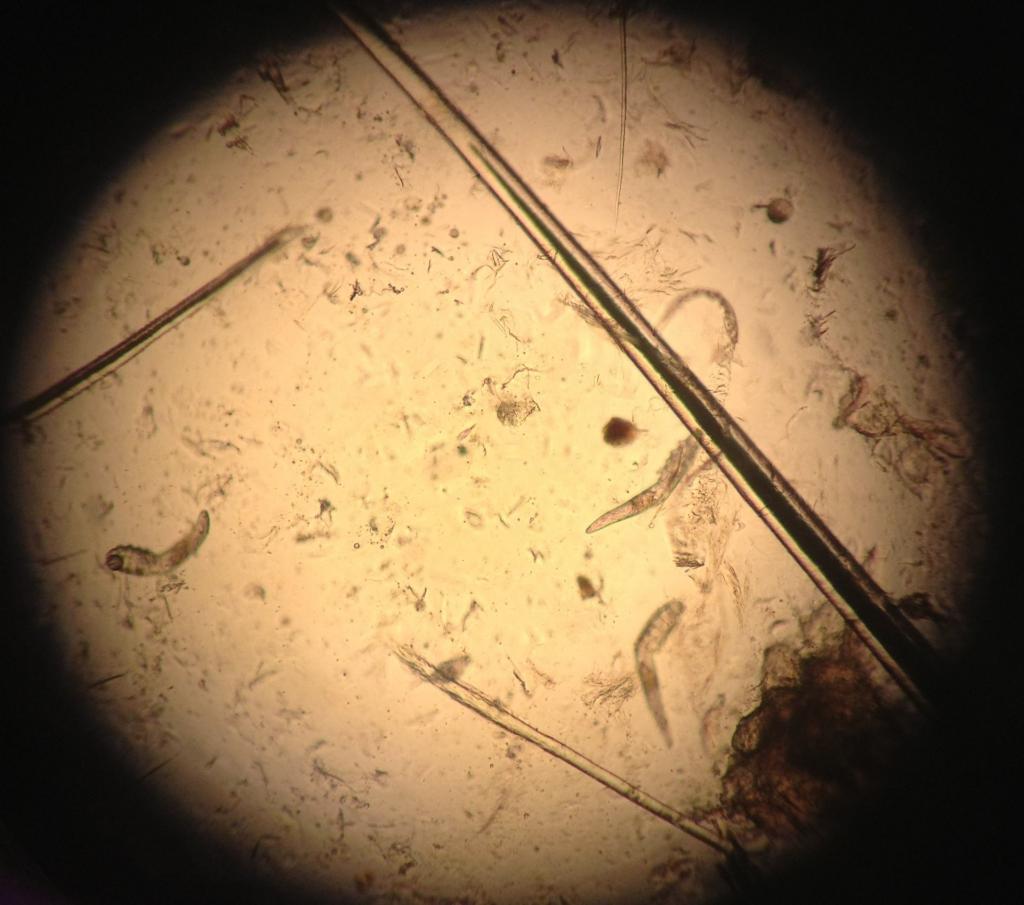

Анализ на клеща демодекс делается просто и безболезненно. Специалист берет соскоб кожи лица или волосяного покрова (брови, ресницы) и отправляет его на исследование в лабораторию. Далее проводится его изучение под микроскопом. Именно так можно увидеть полупрозрачных паразитов и результаты их жизнедеятельности.

Рассматривая под микроскопом составляющие воспалённых образований можно увидеть:

- Клещ демодекс, относится к виду железницы угревой, размножение которого происходит в сальных железах;

- Внешне напоминает тонкого червя прозрачного цвета;

- Оболочка клеща не имеет цвета, но обладает плотностью;

- Размер клеща в среднем 0,4 мм;

- Передвигается кожный клещ с помощью чешуек;

- Питается демодекс клетками кожи и подкожным жиром.